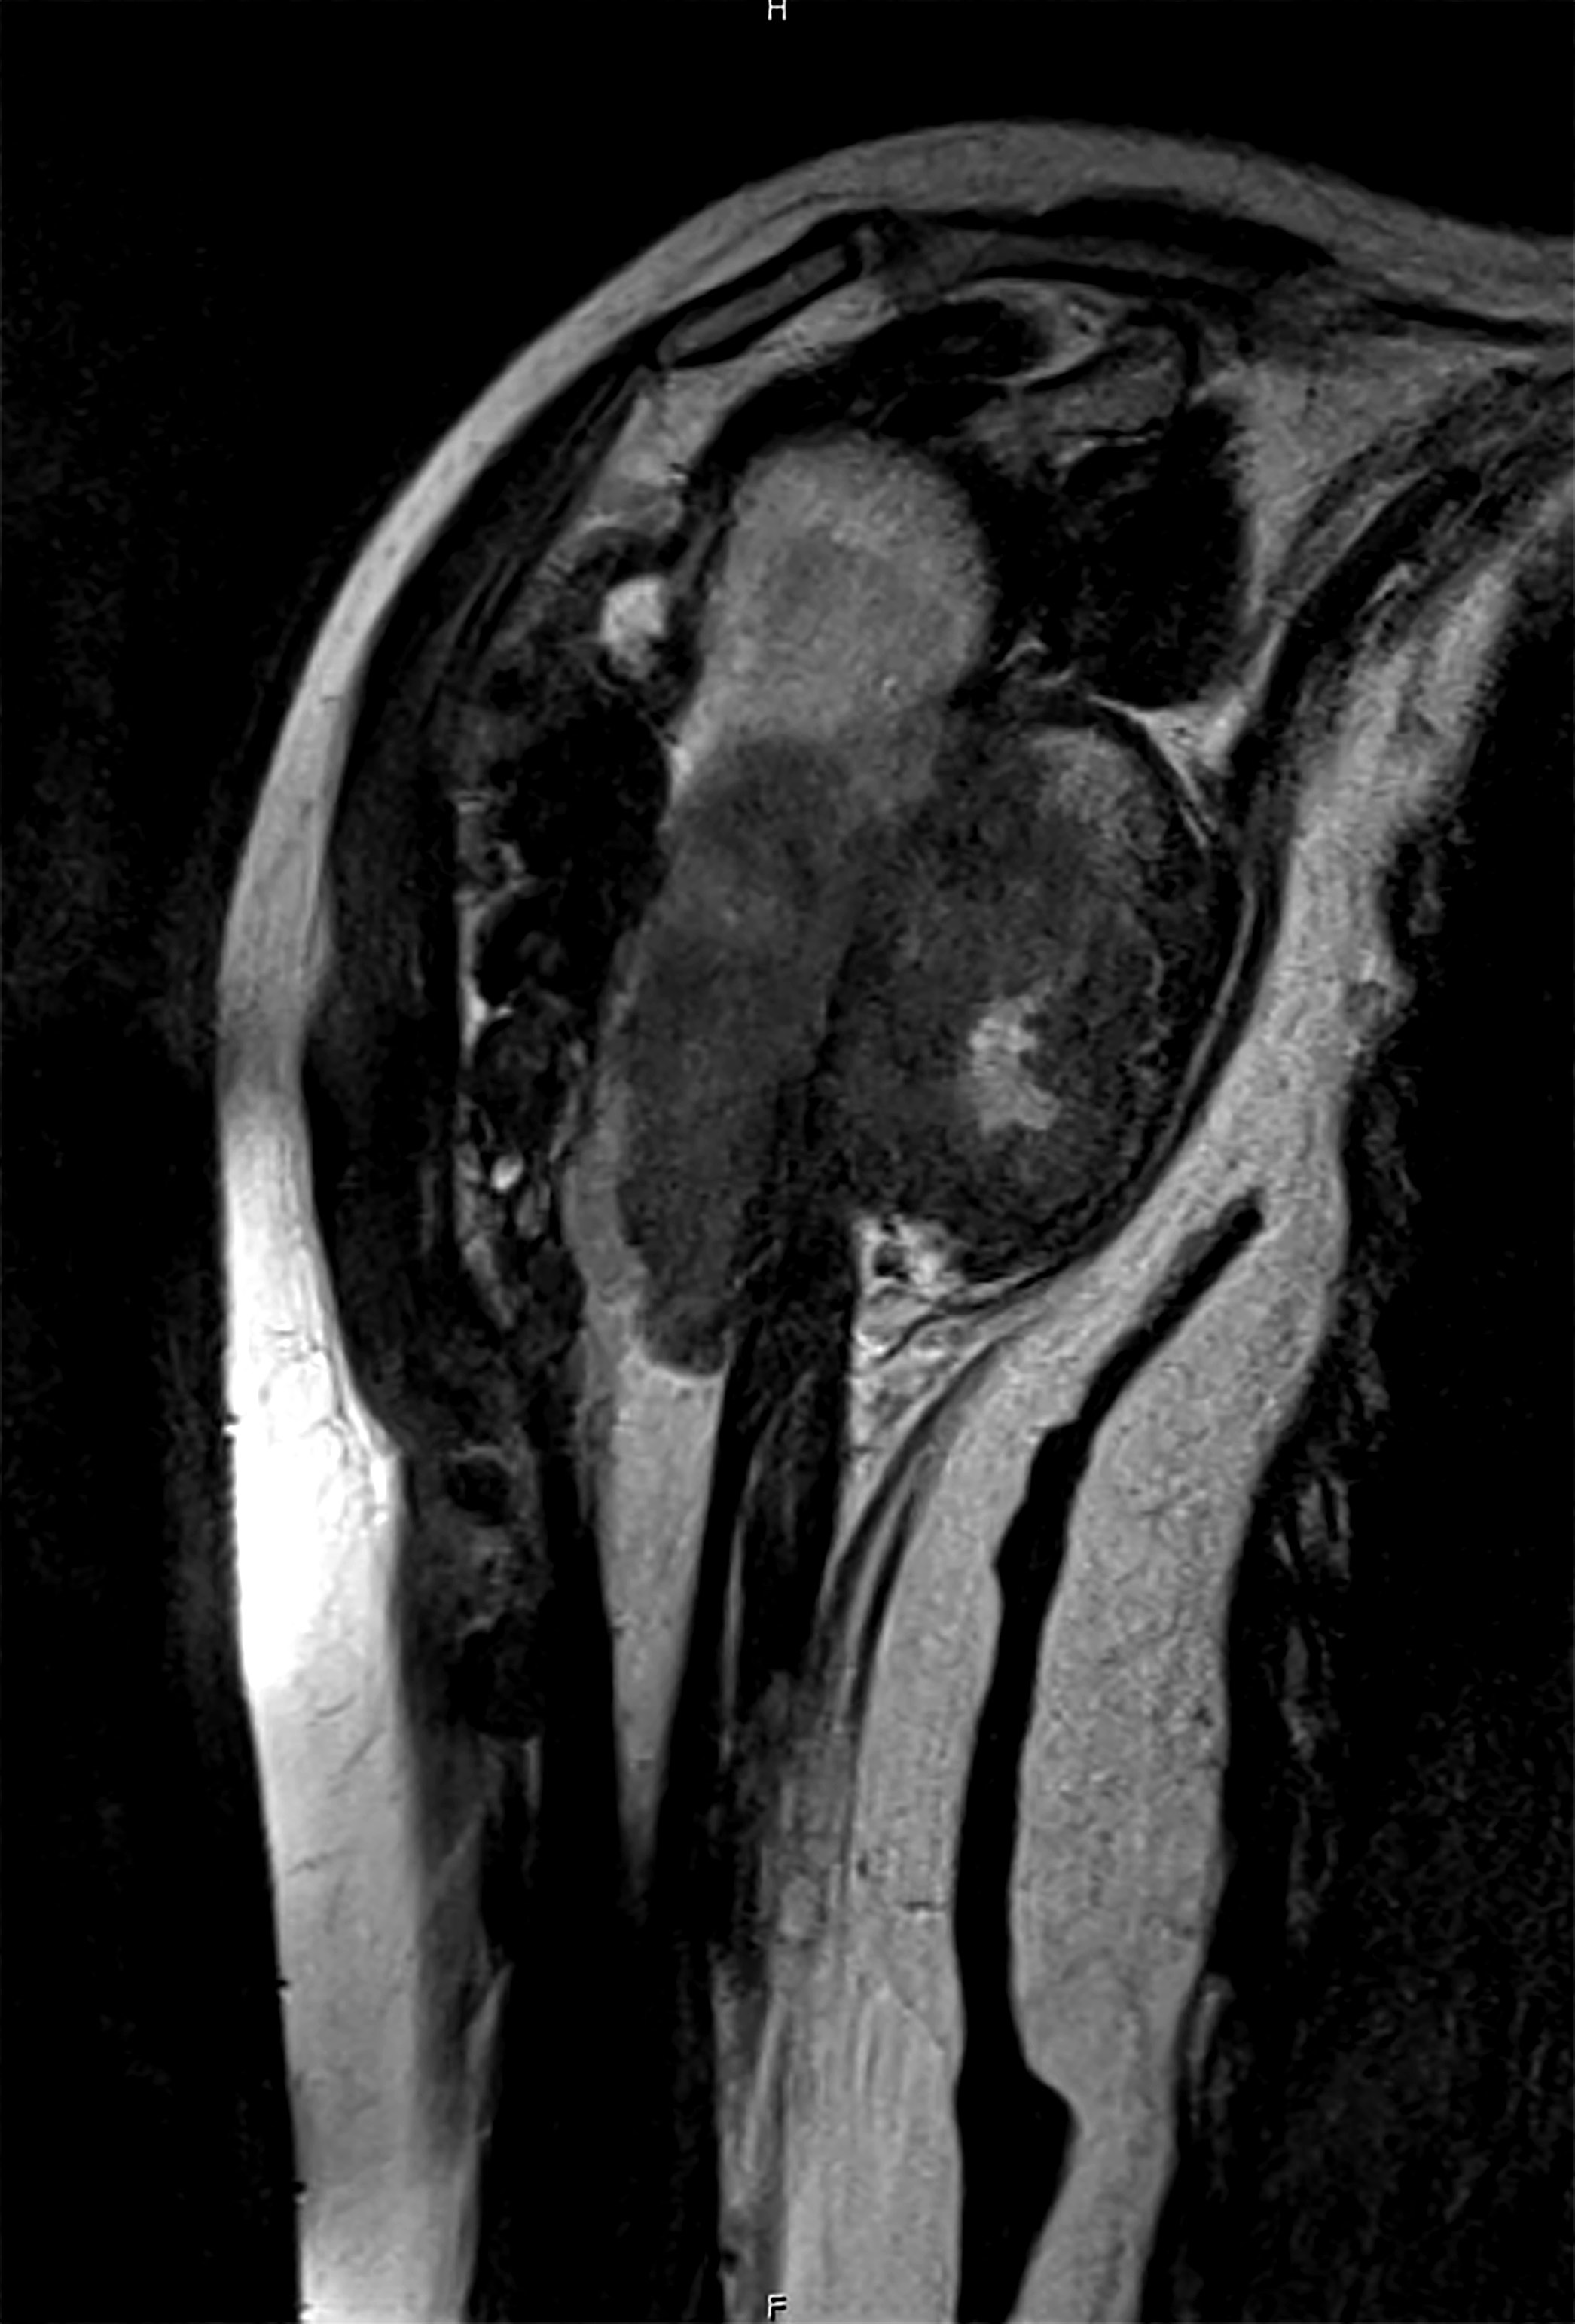

- Conventional central osteosarcoma (Radiographics 2010;30:1653):

- Medullary and cortical bone destruction

- Wide zone of transition, permeative appearance

- Aggressive periosteal reaction

- Sunburst type

- Codman triangle

- Lamellated (onion skin) reaction

- Tumor matrix ossification / calcification

- Soft tissue involvement

Radiology images

Practice question #2

A 16 year old boy had a biopsy from a 16 cm mass in the proximal humerus (see image). Which of the following is true?

Practice answer #2

C. Treatment will include neoadjuvant chemotherapy followed by resection. This is a conventional high grade osteosarcoma.